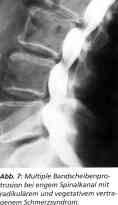

Fall 3: Männlicher Patient. Seit zehn Jahren Rückenschmerzen. Zuletzt Gehstrecke weniger als 100 Meter. Lasegue bei 40 Grad beiderseits positiv. Multisegmentale Fusionsoperation im anderen Krankenhaus wegen schwerer kardialer Schädigung bei Koronarkrankheit abgelehnt. Diagnose: multiple Bandscheibenprotrusionen bei engem Spinalkanal mit radikulärem und vegetativem vertragenem Schmerzsyndrom (Abb. 7). Nach polysegmentaler L 2/3, 3/4, 4/5 und 5/S1 - perkutaner Lasernukleotomie - schlagartige Besserung des Befundes mit negativem Lasegue und wieder freier Gehstrecke. Kontrolle nach sechs Wochen: unverändert positiver Befund. Zwei-Jahres-Kontrolle: gelegentliche Rückenschmerzen, freie Gehstrecke.